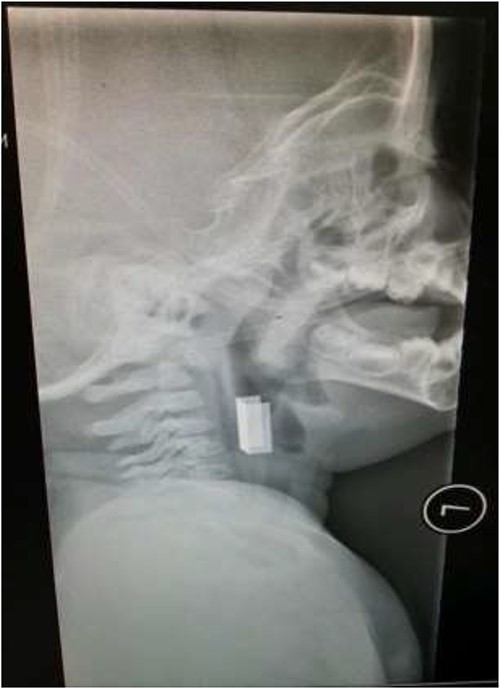

The first case is of a 7-year-old child presenting with a history of barbed wire inhalation. X-ray imaging of his neck and chest showed a radio-opaque object visible in the upper airway with sharp edges (Figs 1 and 2). Due to the position of the foreign body, endotracheal intubation was not feasible. A trial of apnoeic oxygenation using high-flow nasal oxygenation was used as an alternative, and this allowed for an unobstructed view of the larynx, facilitating the safe removal of the foreign body (Fig. 3).

Lateral neck X-ray showing a radio-opaque object with sharp edges visible.